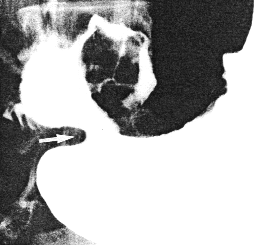

Case 34.1 G.C., l7 year old male, had a two year history of epigastric pain, vomiting, weight loss and retardation of growth. Physical examination revealed severe iron deficiency anaemia. Radiographic study showed multiple lobulated filling defects in the corpus and sinus of the stomach, constant irregularity of the greater and lesser curvatures and a narrowing at the commencement of the pyloric sphincteric cylinder, in the region of the left pyloric loop (Fig. 34.1). The cylinder was partially contracted throughout the examination, never contracting or relaxing maximally; this was associated with a patent pyloric aperture measuring 4.0 mm in diameter. Gastric emptying of fluid barium was delayed. Endoscopy showed diffuse, nodular infiltration of the entire corpus and "antrum", with contact bleeding. The infiltration surrounded the pyloric orifice, which was patent. The duodenum could not be visualized. Histology, according to the "Working Formulation", revealed a high grade, malignant, non-Hodgkin lymphoma. Bone marrow biopsy was normal.

| Fig. 34.1. Case G.C. Irregularities of lesser and greater curvatures extending to commencement of pyloric sphincteric cylinder. Cylinder partially contracted (arrows). Pyloric aperture patent |

Although primary malignant lymphoma may occur anywhere in the stomach, several authors commented on the fact that the pyloric region is the site most commonly affected (Naqvi et al l969; Meyers et al. l975; Lim et al. l977). It usually develops from lymphoid tissue in the mucosa (Ming l973), submucosa (Hricak et al. l980) or lamina propria (Sandler l984). In the early stages peristalsis may be impaired (Ngan and James l973), but it is usually not completely absent (Zornoza and Dodd l980), as the muscular layer is not infiltrated till a late stage (Sandler l984). In Case 34.1 radiographic examination showed widespread infiltration of the proximal part of the stomach, extending as far as the commencement of the pyloric sphincteric cylinder, which was in a state of partial contraction with absent cyclical activity; this is an uncommon presentation of malignant gastric lymphoma. In Case 34.2 there was radiographic and operative evidence of widespread involvement of the distal stomach, including the pyloric sphincteric cylinder and the first part of the duodenum, with destruction of normal anatomical features. The failure of cyclical activity of the sphincteric cylinder may be expected to hamper propulsion and trituration of solids.